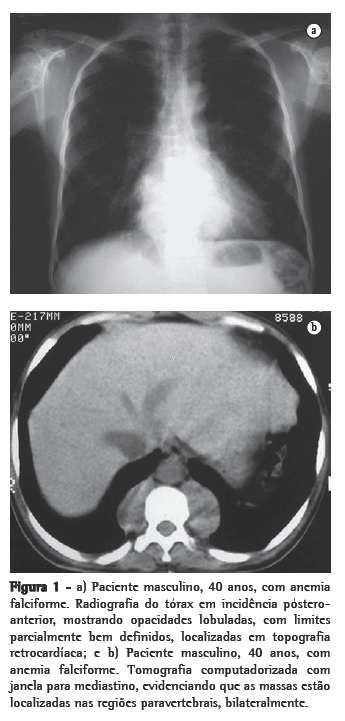

Como achados associados, dois pacientes mostravam calcificações no baço (Figura 4). Ambos eram portadores de anemia falciforme. Dos seis pacientes, dois haviam sido esplenectomizados, e em dois a imagem do baço era normal. Alterações ósseas relacionadas à doença de base foram identificadas em três pacientes.

Através da TC, podem ser observadas massas com densidade de partes moles, em sua maioria homogêneas, com características semelhantes às descritas na radiologia convencional,(1,2,5,6) que podem ou não ser realçadas após a administração do meio de contraste.(4,10) Este método de imagem é importante para analisar a estrutura interna das lesões, particularmente quando ricas em gordura,(5) para avaliar a presença de outras massas paracostais e para detectar alterações ósseas associadas a certas doenças hematológicas, como a talassemia e a anemia falciforme.(6) Nos casos relacionados a talassemia, anemia falciforme ou metaplasia mielóide, pode ocorrer um alargamento das cavidades medulares das costelas.(5)

Todos esses aspectos foram identificados em nossos casos. É interessante ressaltar que os achados em dois pacientes mostravam calcificações no baço, decorrentes de infartos múltiplos, com autoesplenectomia. Ambos eram portadores de anemia falciforme. Esse achado pode também auxiliar no diagnóstico diferencial.